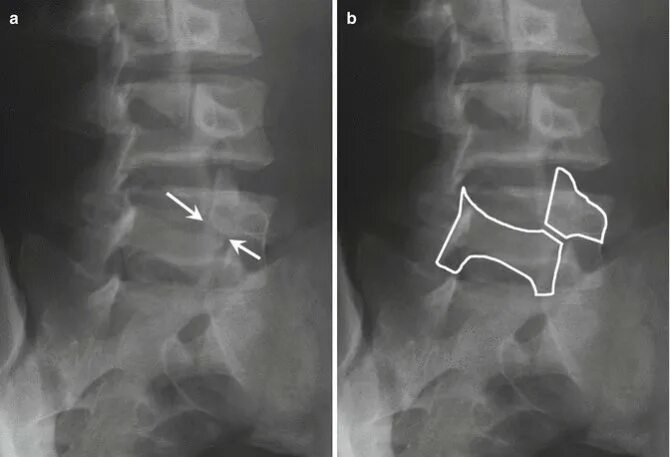

Смещение позвонков поясничного операция